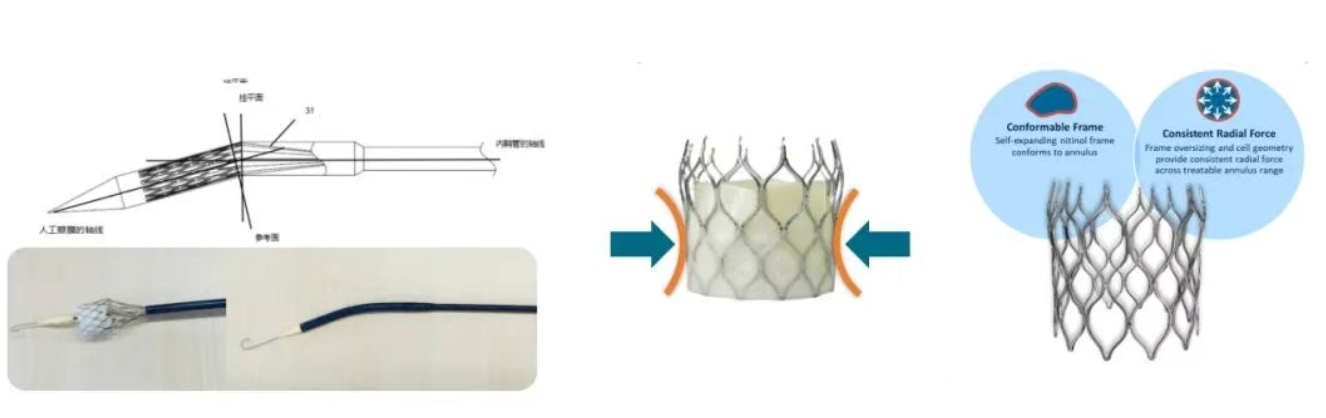

✅预弯型设计:装载后瓣膜与系统成角度挂载,配合短瓣架柔性连接设计,自动适应主动脉弓弯形,轻松通过小弓角等挑战弓部,同时能够自动调整跨瓣角度,减少辅助器械和补救器械的使用。(第一例72°横位心,第二例67°锐角弓,均未使用snare辅助)。

✅以上两例患者均为高钙化二叶瓣患者,最终均获得较好的血流动力学表现。ScienCrown全瓣架参与支撑,提供充足的径向支撑力,同时可兼顾顺应性,刚柔并济,完美适配高钙化与二叶瓣患者特征,临床试验二叶瓣患者比例高达63.28%,重度钙化比例高达54.69%,一年随访有效瓣口面积1.88cm2。

该批手术的成功再次印证了我国结构性心脏病TAVR领域的突破性进展,其核心在于技术路径的精准把控与创新器械的协同应用。作为国产高端医疗器械的创新代表之一,乐普心泰ScienCrown瓣膜采用创新短支架自膨胀设计,融合了“自膨瓣”与“球扩瓣”的双重优势。其输送系统的预弯型设计显著提升了瓣膜的通过性与植入的同轴性,与常规自膨胀瓣膜仅能部分释放不同,该款瓣膜支持100%完全释放,便于术者直观评估瓣膜形态及其对冠脉的影响,有效规避了传统自膨胀瓣膜因同轴性不足带来的二次位移风险,达成了瓣膜位置的可控调节。这一创新TAVR系统,不仅实现了国产瓣膜锚定、瓣膜释放及临床效果等方面的进化发展,更为复杂解剖结构患者提供了兼具安全性与操作确定性的治疗新方案。